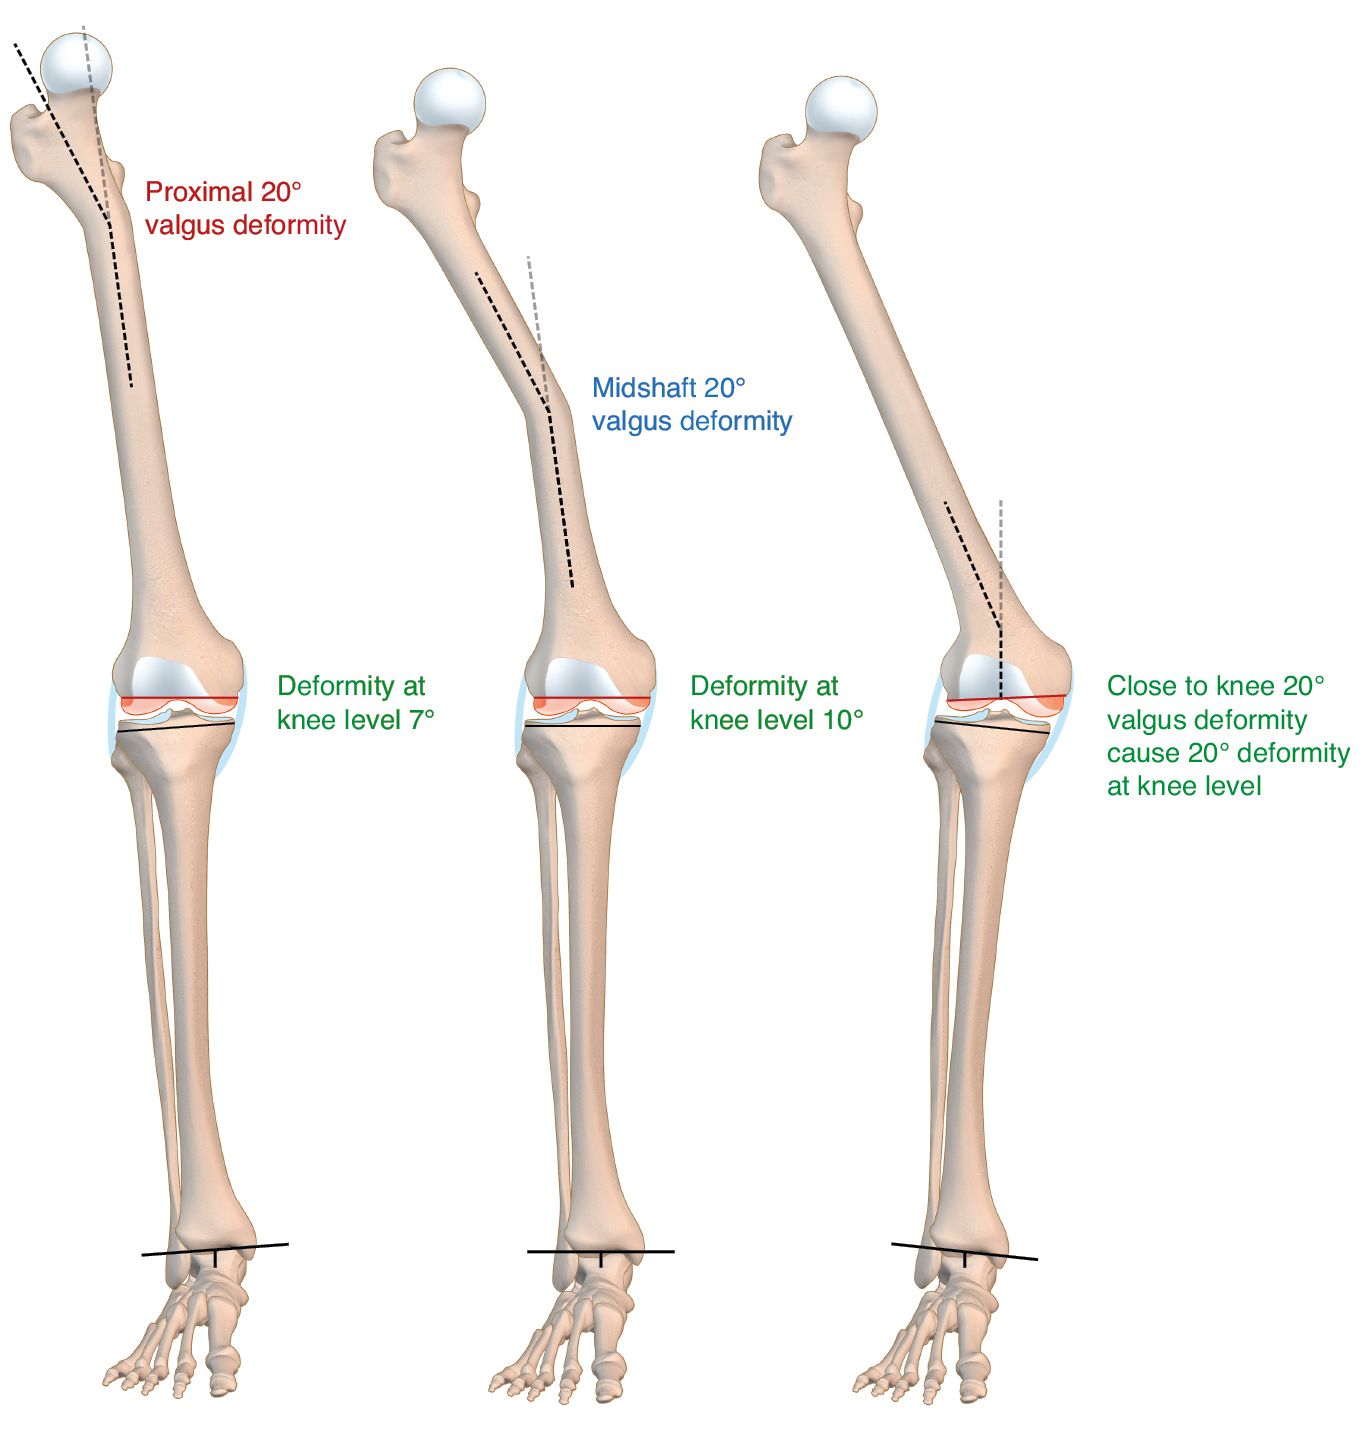

It is essential to know the aetiology of the deformity and its location regarding the knee in order to evaluate its real influence on the mechanical axis of the limb. [1], Jeffery RS, Morris RW, Denham RA Coronal alignment after total knee replacement. JBJS Br 1991;73(5):709.[3], Panayiotis JP, Karachaloios T, Themistocleous GS Total knee arthroplasty in patients with pre-existing fracture deformity. Orthopedics. 2007;30(5):373.[4] Wolff AM, Hungerford DS, Pepe CL The effect of extraarticular varus and valgus deformity on total knee arthroplasty. Clin Orthop. 1991;271:35-51. The nearer to the joint the deformity is, the more it will affect the mechanical axis and the intraarticular bone correction cuts (1/3 third rule – Figure 4).

The approach of correcting the axis through intra-articular unusual bone cuts and soft tissue release offers advantages, as it requires only one surgery, allows a faster rehabilitation and avoids the possible complications of a complementary osteotomy (non-union, infection and hardware failure) or of the ligament tightening proposed by Wolff. [4] Wolff AM, Hungerford DS, Pepe CL The effect of extraarticular varus and valgus deformity on total knee arthroplasty. Clin Orthop. 1991;271:35-51. In our opinion, ligament retightening is not a good option to achieve stability after any TKA and least of all in these difficult cases. Some authors consider that when the deformity exceeds 10º in the tibial or femoral coronal plane, special considerations apply due to the resulting complex instability. [3], Panayiotis JP, Karachaloios T, Themistocleous GS Total knee arthroplasty in patients with pre-existing fracture deformity. Orthopedics. 2007;30(5):373.[13], Papadoupolos EC, Parvizi J, Lai CH Total knee arthroplasty following prior distal femoral fracture. Knee. 2002;9(4):267-74.[14], Lonner JH, Siliski JM, Lotke PA Simultaneous femoral osteotomy and total knee arthroplasty for osteoarthritis associated with severe extra-articula deformity. JBJS Am. 2000;82(3):342-348.[17] Roffi RP, Merrit PO Total knee replacement after fracture about the knee. Orthop Rev. 1989;19(7):614-620. Even if there is no consensus, in our experience and most publications recommend that unusual bone cuts can be used in patients with femoral deformities in the coronal and/or sagittal plane of up to 20º. Regarding the tibia, deformities of up to 30º in the coronal plane can also be treated this way. [7],Incavo SJ, Kapadian C, Torney R Use of an intramedullary nail for correction of femoral deformities combinated with total knee arthroplasty. Jour Arthroplasty. 2007;22(1):133.[3], Panayiotis JP, Karachaloios T, Themistocleous GS Total knee arthroplasty in patients with pre-existing fracture deformity. Orthopedics. 2007;30(5):373.[6]Wang JW, Wang CJ Total knee arthroplasty for arthritis of the knee with extra-articular deformity. JBJS Am. 2002;84(10):1769-1774. It should also be remembered that, when the deformity gets closer to the knee, its impact increases due to its effect on the intra-articular bone cuts.[4] Wolff AM, Hungerford DS, Pepe CL The effect of extraarticular varus and valgus deformity on total knee arthroplasty. Clin Orthop. 1991;271:35-51.